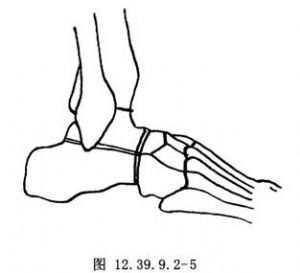

1.在足外侧沿皮肤皱褶做一斜行切口,切口中心位于跗骨窦表面,于后外侧距舟关节水平起自趾长伸肌腱的外侧缘(图12.39.9.2-4)。向后延长切口,弯向跖侧,止于腓骨肌腱水平。仔细保护伸肌腱与腓骨肌腱,沿切口经跗骨窦锐性切至趾短伸肌。将趾短伸肌起点连同跗骨窦内的脂肪一起翻向远侧,清除跗骨窦所有的残余软组织,显露距下、跟骰关节以及距舟关节的外侧部分。

3.找到跟骨的前关节突,沿跗骨窦底面水平将其切除,以便更好地显露所有关节。做此项截骨时,用骨刀平行足底面截骨,保留切下的骨以备植骨用。然后,用骨刀去除跟骰关节的关节面以显露松质骨。除非需要楔形切骨以矫正骨性畸形,否则一般在两侧去除等量的骨质(图12.39.9.2-4)。用直的和弧形骨刀去除距骨头远侧部分,显露距头松质骨的骨质即可。可插入小的椎板撑开器,以便获得更好的显露。可能需要在内侧另做一切口以显露距舟关节的最内侧部分。去除舟骨的近侧关节面和软骨下骨,修整其表面并使其变粗糙,以便与距骨紧密贴合(图12.39.9.2-5),切除载距突的关节面及距下关节的前关节面。